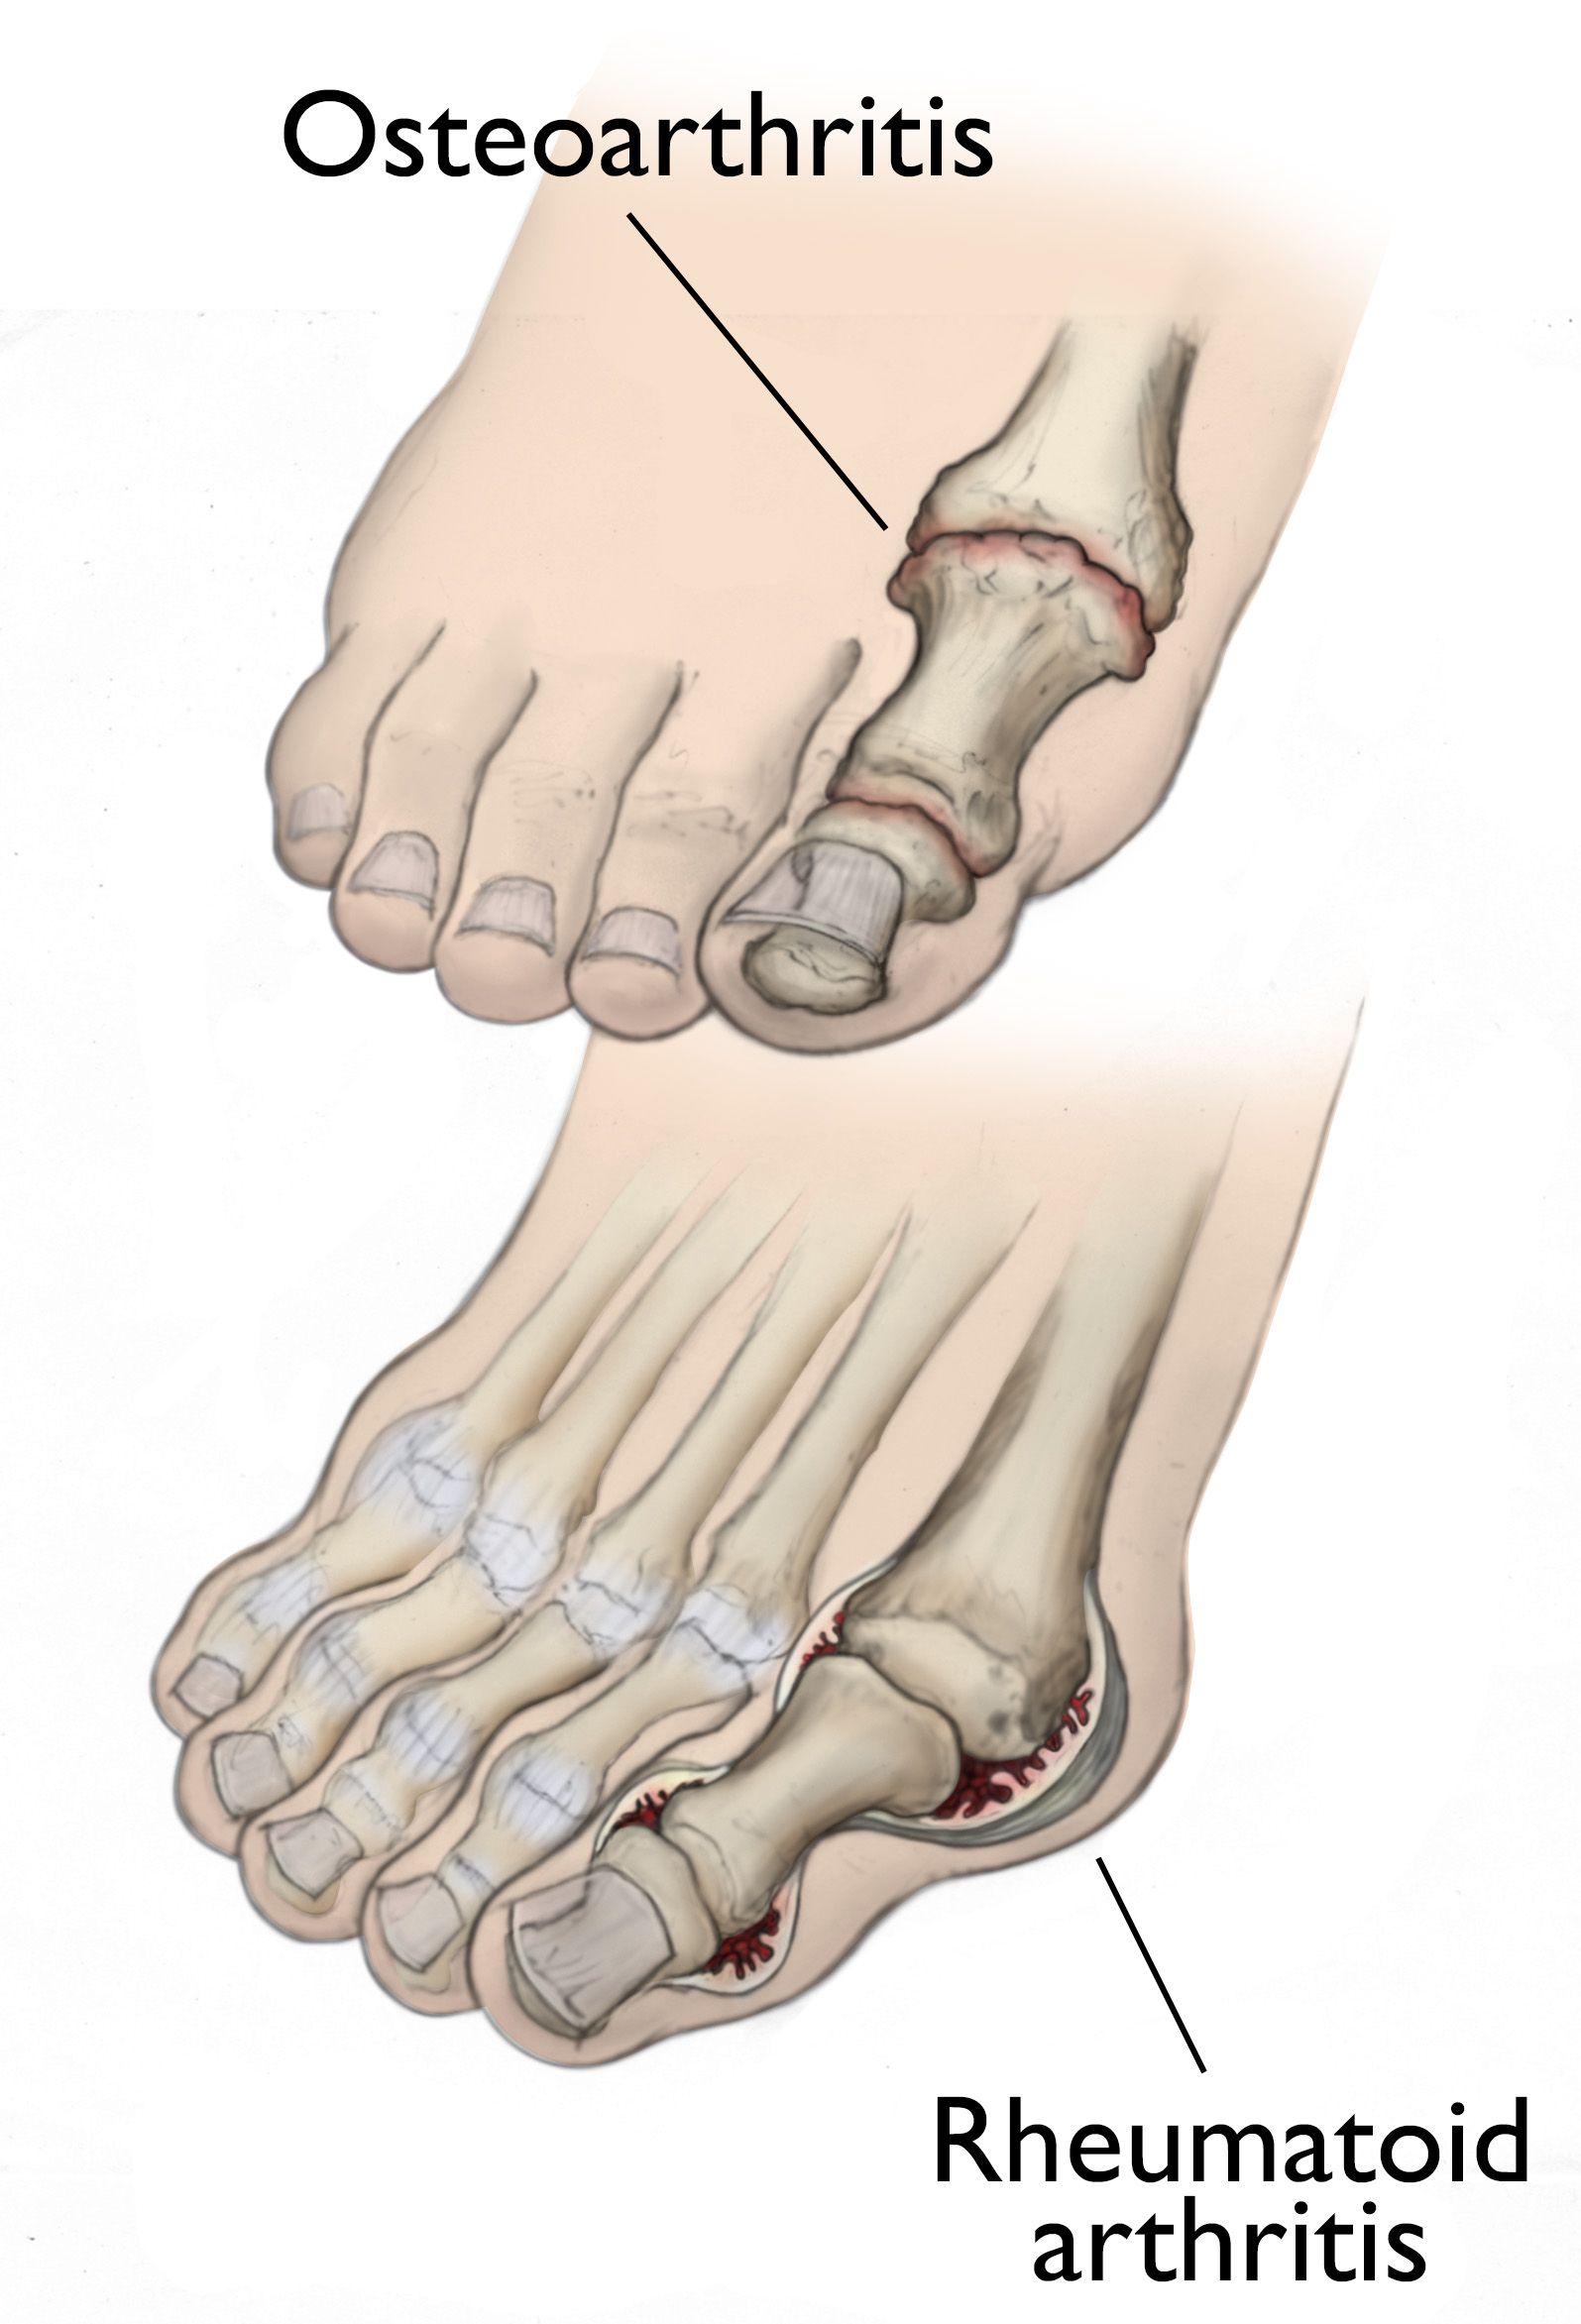

illustrations of osteoarthritis and rheumatoid arthritis of the big toe

(Top) Osteoarthritis that has progressed to bone rubbing on bone and bone spurs. (Bottom) Swollen, inflamed synovium and joint deformity are signs of rheumatoid arthritis.

Reproduced and modified from The Body Almanac. © American Academy of Orthopaedic Surgeons, 2003

Osteoarthritis

Osteoarthritis, also known as degenerative or wear-and-tear arthritis, is a common problem for many people after they reach middle age, but it may occur in younger people, too.

In osteoarthritis, the cartilage in the joint gradually wears away. As the cartilage wears away, it becomes frayed and rough, and the protective space between the bones decreases. This can result in bone rubbing on bone and produce painful osteophytes (bone spurs).

Rheumatoid Arthritis

Rheumatoid arthritis is a chronic disease that can affect multiple joints throughout the body, and often starts in the foot and ankle. It is symmetrical, meaning that it usually affects the same joint on both sides of the body.

Rheumatoid arthritis is an autoimmune disease. This means that the immune system attacks its own tissues. In rheumatoid arthritis, immune cells attack the synovium covering the joint, causing it to swell. Over time, the synovium invades and damages the bone and cartilage, as well as ligaments and tendons, and may cause serious joint deformity and disability.